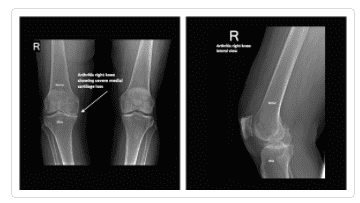

Osteoarthritis of the knee is usually a slowly progressive degenerative disease where the joint cartilage gradually wears away. Because it progresses over time it most often affects older people.

Symptoms typically increase over a period of years. However, the primary symptoms of knee osteoarthritis are mild to severe pain, localized swelling, stiffness, and limited range-of-motion in the knee.

Knee X-ray Gallery

Please visit our knee x-ray gallery to see more images of knees affected by osteoarthritis.